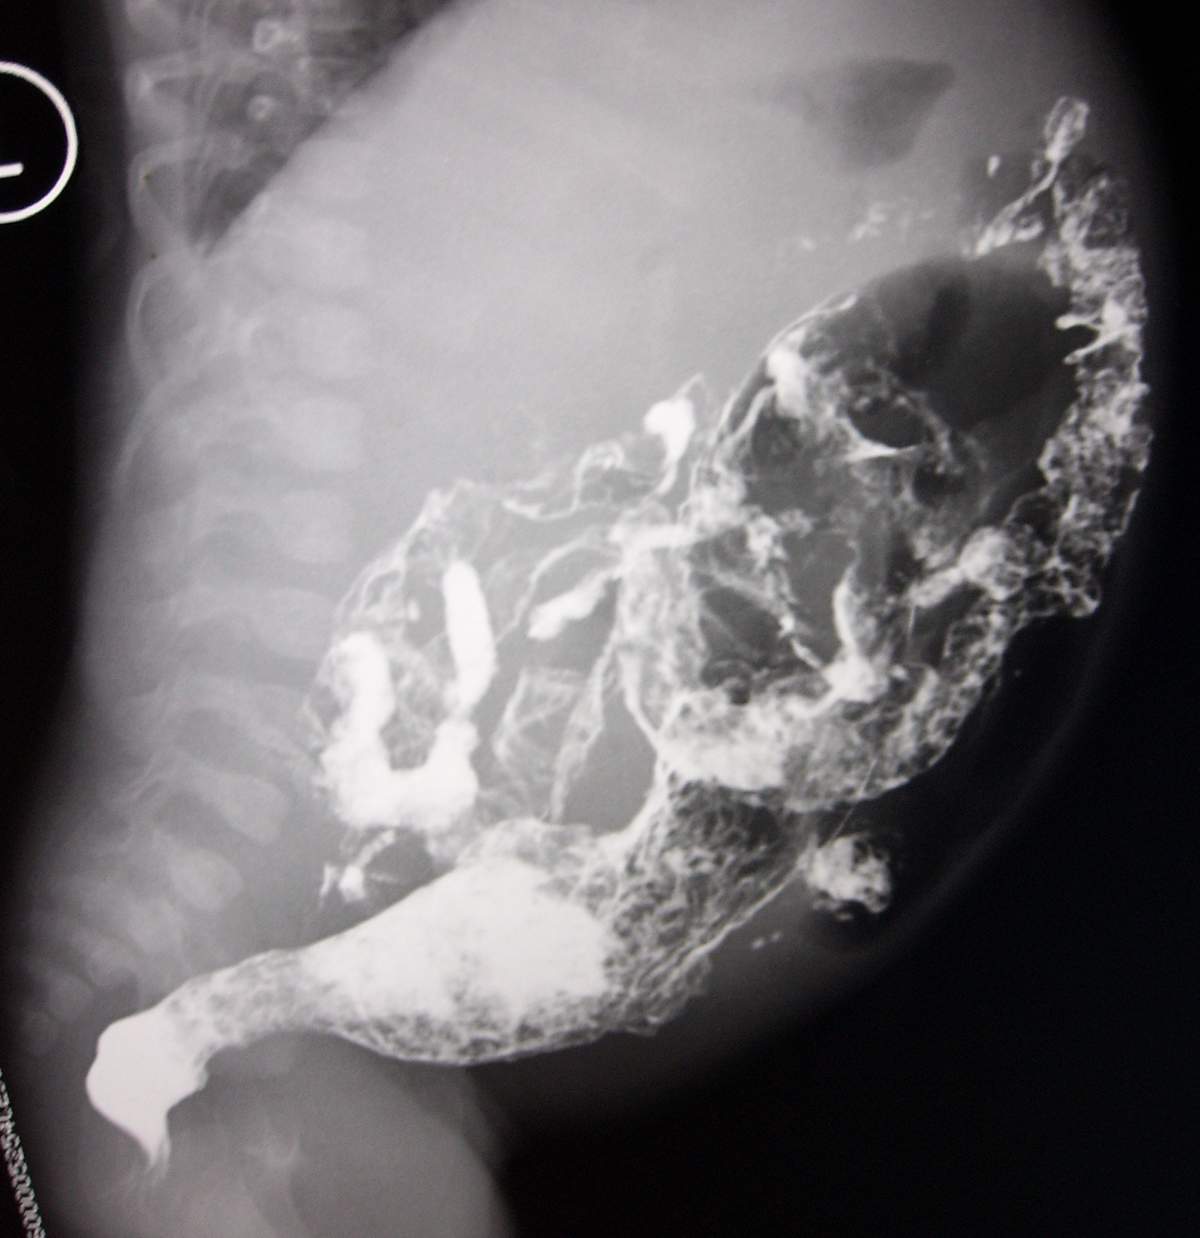

标题: PED0054:[讨论][分享]小儿钡灌肠!

男,2月,腹胀2天。

巨结肠

巨结肠很典型

大家说得都太粗了吧,诊断巨结肠总的说明那一段有问题吧。这样治疗起来才有方向。

我觉得是直肛型的巨结肠,可以先扩扩肛试一下。